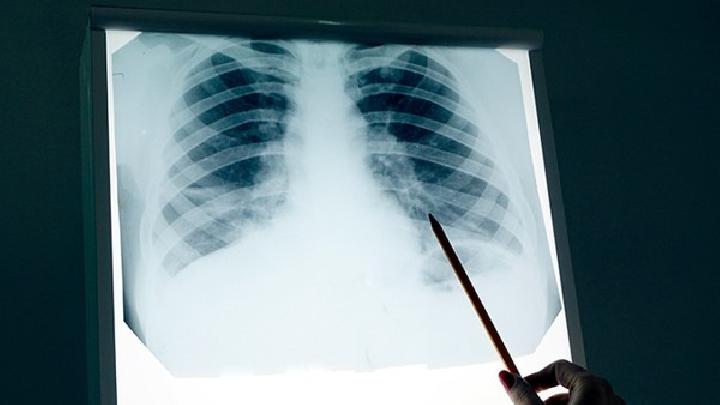

胸部X线检察对老年人肺炎症状的诊断极为重要

胸部X线检察对老年人肺炎症状的诊断极为重要,肺内出现新的浸润灶即可作出诊断,但各种不同的病原体感染的肺部表现却缺乏特征性而不易区分。